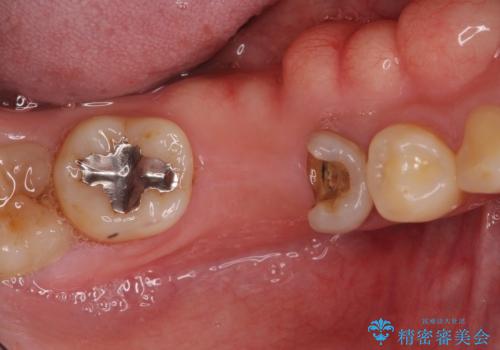

- 右下の欠損部の治療を希望して来院された患者様です。

部分矯正を行った後にインプラント埋入と手前の歯の根管治療を行い、その後補綴治療を行うこととしました。

治療途中より、上の歯や反対側の銀歯、上顎前歯の色合いや下顎前歯のデコボコが気になってきたため、全てを治療することとしました。